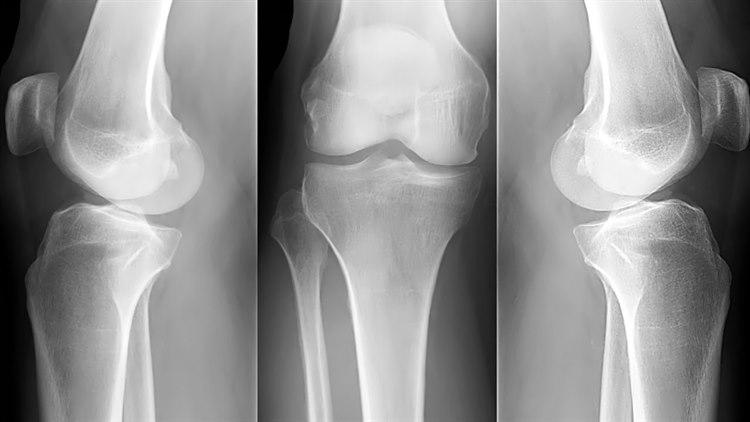

Beinvev framstilles tydelig på røntgenbilder. Bløtvevet rundt beinvevet framstilles som skygger av varierende tetthet, mens hevelser og forkalkninger kan ses på røntgen. Brusk, leddbånd og sener lar seg ikke fremstille direkte på røntgen.

Gode røntgenbilder forutsetter at området som avbildes holdes i ro. Som regel er det nødvendig å ta bilder fra minst to retninger for å få en tilfredsstillende fremstilling av beinet. Vanligvis tas disse vinkelrett på hverandre - vanligvis forfra/bak og sidebilde (jfr. albue front og albue side nedenfor). Mer detaljert informasjon om et bein vil kunne kreve flere projeksjoner, f.eks. skråbilder.

Røntgen av beinvev kan fremvise en rekke funn. De vanligste funnene er: